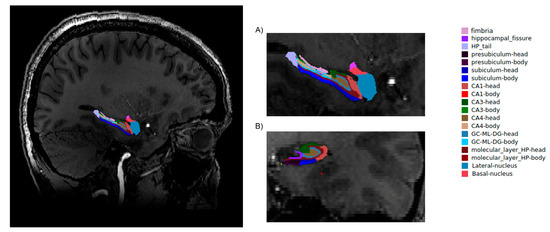

2.3. Image Analysis